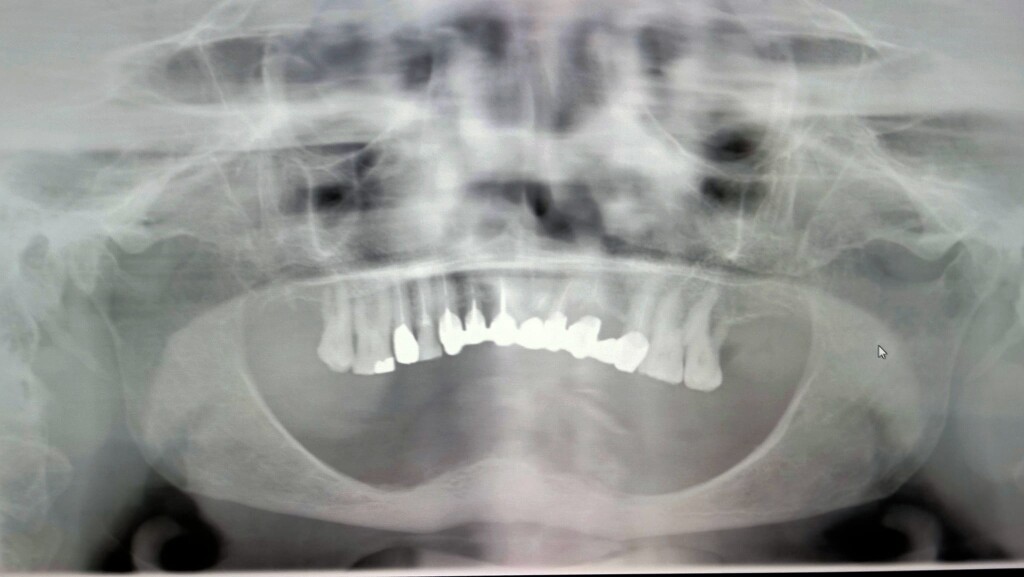

Mandibola atrofica Formazione Odontoiatrica

La domanda era se, secondo me, si potesse eseguire una riabilitazione fissa su impianti. Questo articolo, e soprattutto il video che segue, vogliono essere i miei suggerimenti al collega e a chiunque altro volesse ritenerli utili.

Parleremo del trattamento di questa mia paziente, trattata cinque anni fa, che mi sembra molto simile a quello del collega.

Mandibola atrofica Formazione Odontoiatrica 2